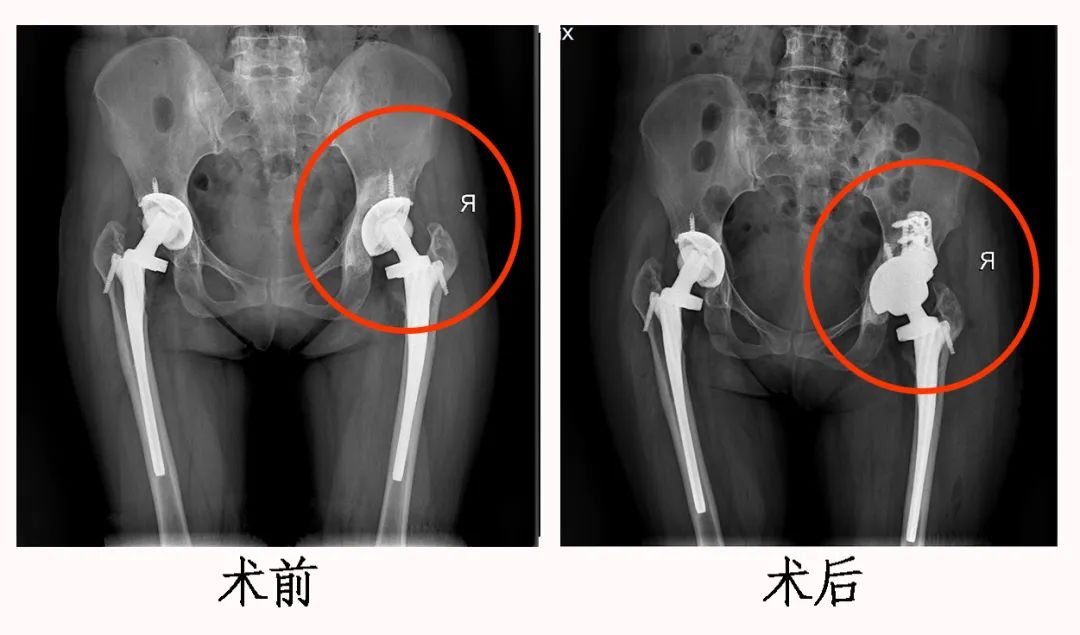

无独有偶,2007年,二十出头的夏女士因 双侧股骨头坏死进行双侧髋关节置换术 ,2014年开始出现右侧髋关节疼痛。由于多年的“负重前行”,夏女士体内的假体已经偏离了本该“坚守”的位置,后来在其他医院诊断为右侧髋关节假体松动。

棘手的是,因夏女士髋臼周围剩余骨质极少,翻修难度太大,失败风险极高,多家医院均不敢进行手术治疗,这不仅给患者造成了精神和生活压力,给医生也带来了巨大的挑战。

2021年,夏女士向襄阳市中心医院 骨科二病区 梅荣成团队求助。如何填补髋臼骨缺损?如何恢复髋关节正常的解剖位置?如何稳定地重建髋关节假体?每一个问题都需要充分成熟的思考和准备。 为了完成这一高难度髋关节翻修手术,梅荣成根据患者髋臼剩余骨质情况,不仅打印出患者病髋模型,还针对患者骨质缺损打印出合适的钽金属块,用于填补骨缺损,增加假体稳定性。

一切准备就绪,手术如期进行,团队按照术前设计,顺利完成翻修手术,真正实现了髋关节“ 私人订制”。